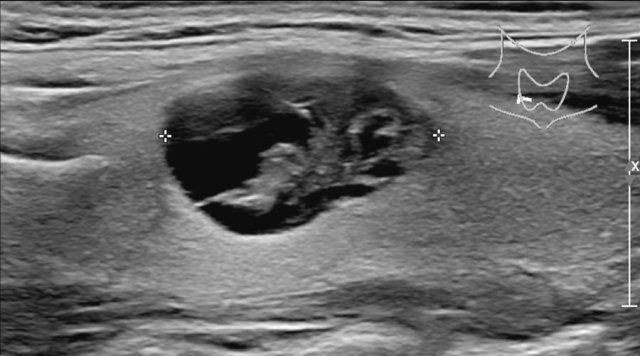

Mixed cystic/solid

In mixed cystic/solid lesions the amount of cystic and solid parts is not important.

This lesion gets 1 point for the mixed cystic/solid composition.

There is a mixed composition with a cystic component in the center.